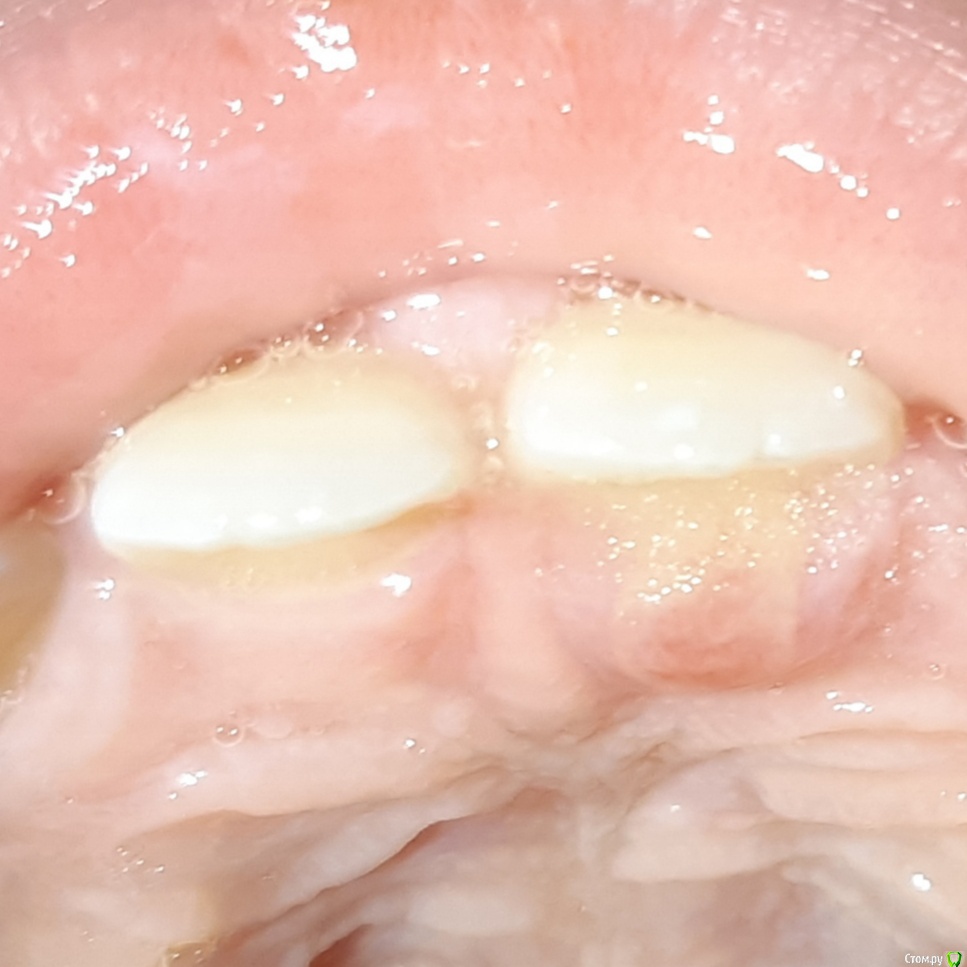

ANCHOUSE Опубликовано 29 марта, 2019 Поделиться Опубликовано 29 марта, 2019 (изменено) Здравствуйте! Буду благодарна за рекомендации по дальнейшей тактике.Пациентка, 7 лет. На фоне ОРВИ в начале марта 2019г. обратили внимание на отечность, гиперемию десны вестибулярно в области 21, 22з., небольшую подвижность 21з.Небно в области 21з. разрастание грануляционной ткани. Сначала думали,что стоматит или травма в школе. Потом выявили перекрестный прикус с глубоким резцовым перекрытием и соответственно травму в области 21з. Изготовили пластинку с винтом на нижнюю челюсть.Неделю с пластинкой 24 часа в сутки, еда тоже. Полоскания,обработка 0.2%ХГ, асепта .Изменений в лучшую сторону в области травматического элемента нет.Ребенка ничего не беспокоит. С вестибулярной стороны гиперемия и отек стали меньше.Что предпринять? Убрать грануляции небно? Изменено 29 марта, 2019 пользователем ANCHOUSE Ссылка на комментарий

ANCHOUSE Опубликовано 29 марта, 2019 Автор Поделиться Опубликовано 29 марта, 2019 (изменено) Проверяли,нормаПеркуссия одинаковая,безболезненнаяПочему проф.чистку? То, что вы принимаете за налет(?) на небной поверхности 21, это и есть зона интереса Изменено 29 марта, 2019 пользователем ANCHOUSE Ссылка на комментарий

ANCHOUSE Опубликовано 30 марта, 2019 Автор Поделиться Опубликовано 30 марта, 2019 Может инородное тело?Тоже была у меня такая версия....Получается надо убрать грануляции и смотреть? Так ничего не видно, зондом пародонтологическим проверяли... Ссылка на комментарий

Nazim_NV86 Опубликовано 31 марта, 2019 Поделиться Опубликовано 31 марта, 2019 Можно поконкретнее? Почему уже пора?Мы тут пока не можем определиться ,что происходит вообще....Напомню ребенку 7 летПотому что там костный карман + ложный с элементом воспаления. Какие из новообразований мы надеемся там увидеть ? Конечный итог разве не приведёт к его иссечению? Получается надо убрать грануляции и смотреть?Так ничего не видно, зондом пародонтологическим проверяли...Зонд нащупает только крупное. Если это образование отодвинуть пинцетом и с увеличением осмотреть карман? Ссылка на комментарий

ANCHOUSE Опубликовано 31 марта, 2019 Автор Поделиться Опубликовано 31 марта, 2019 Потому что там костный карман + ложный с элементом воспаления. Какие из новообразований мы надеемся там увидеть ? Конечный итог разве не приведёт к его иссечению? Зонд нащупает только крупное. Если это образование отодвинуть пинцетом и с увеличением осмотреть карман?Согласна. Предположительно очаговую фиброзную гиперплазию вследствии травмы.Скорее всего приведет. Вопрос об отношении к кости.Затронута/нет Попробую осмотреть с увеличением. Ссылка на комментарий